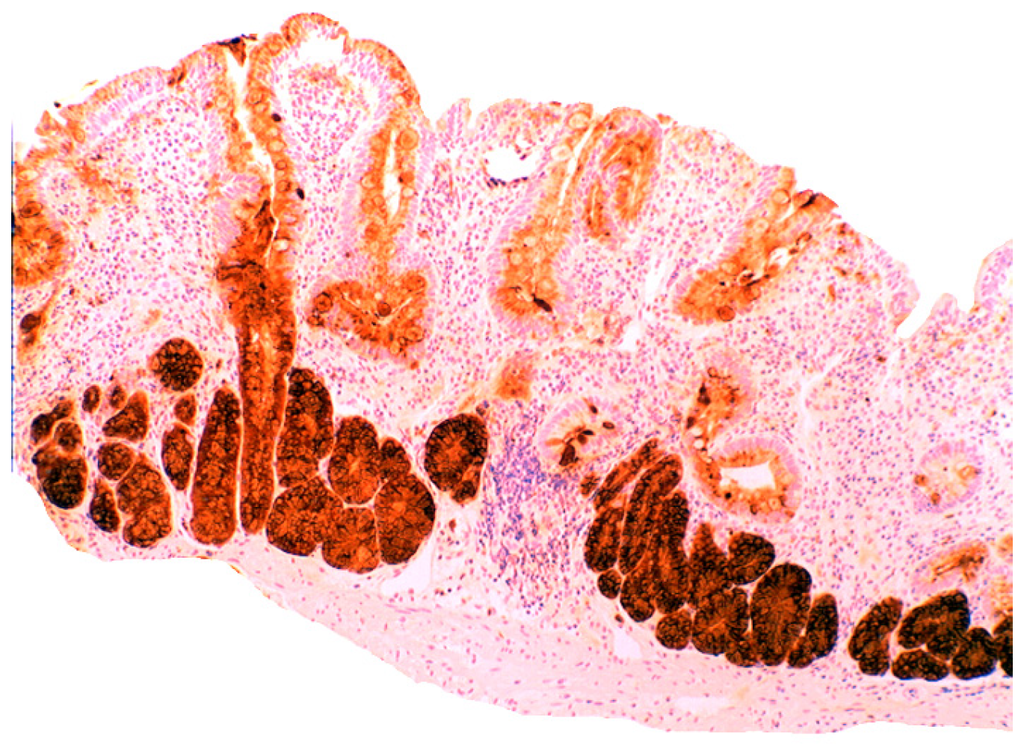

In the normal duodenal mucosa, Paneth cells produce lysozyme. In coeliac disease, lysozyme is up-regulated in goblet cells, in dilated crypts with mucus-metaplasia (Figure 9), a phenomenon more apparent in the bulbus [10] (Figure 10). It is not inconceivable that the lysozyme-rich mucus metaplasia mirror stem cell adaptation to the signals generated by the pathogenic bacteria present in the duodenal microenvironment [63].

Figure 9.

Chronic atrophic duodenitis (celiac disease). Villous atrophy showing lysozyme-rich mucus metaplasia in the lower part of the crypts. Note lysozyme expressing goblet cells (lysozyme immunostain, ×10).

Figure 10.

Chronic atrophic duodenitis (celiac disease). Villous atrophy showing extensive lysozyme-rich mucus metaplasia of the crypts. Note absence of Paneth cells (lysozyme immunostain, ×10).